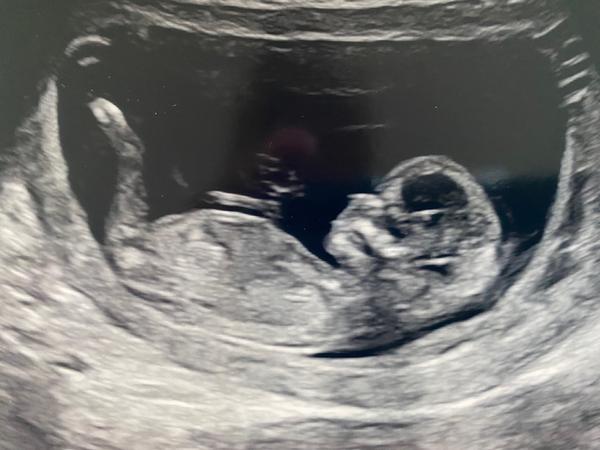

@makronka222 Ruce dokážu lokalizovat, ty mi doktorka na fotce ukázala 🙂. Nohy jsem neviděla, doufám, že je má :D. Já osobně vidím jen rozmazané fleky, ale třeba tu má někdo zkušené oko 🤷♀️.

Z tyhle nekvalitni fotky asi tezko neco vyhledas. Muze tam dole byt ruka, snura, nohy krizem...